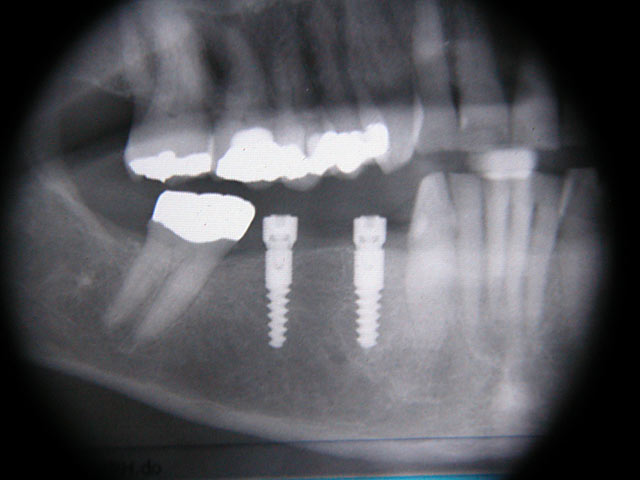

Kurzimplantate und Sofort – Implantate: